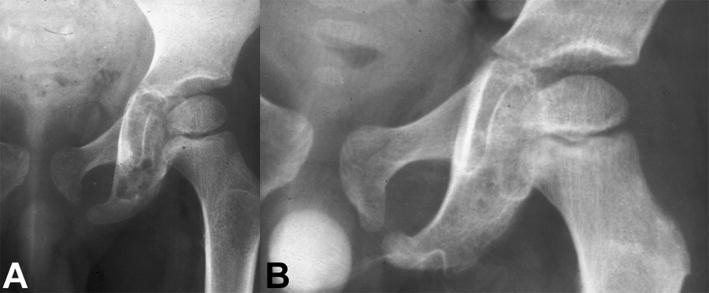

a Anteroposterior radiograph of the pelvis of a 6-year-old boy with a painful osteolytic lesion at the left ischial ramus. CT-guided frozen section biopsy showed eosinophilic granuloma; intralesional methylprednisolone injection was performed. b Anteroposterior radiograph of the pelvis shows complete reconstitution of the lesion 1 year after diagnosis and treatment